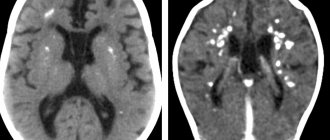

An informative picture is provided by computed tomography and MRI of the brain. With their help, tumors, cystic formations, signs of inflammation, and abscesses are identified.